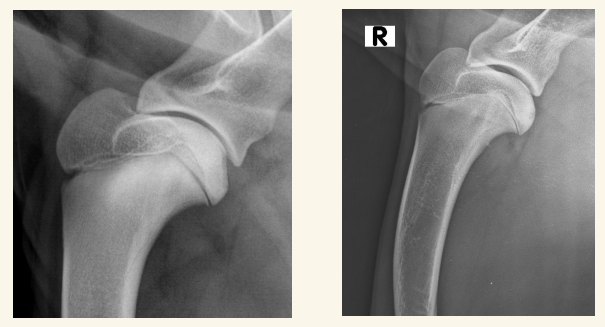

Luxación Coxo-femoral

- Por traumatismo, a veces leve si existe Displasia. Suele aparecer con fracturas de pelvis, uni o bilateral

- Normalmente cráneo-dorsal, aunque puede ser dorsal, ventral, caudal (rara) o intrapélvica

- Mejor 2 proyecciones pero en VD se ve mejor (ilion desplazado, mayor tamaño articular, perdida de contorno liso)

- Tambien hay luxacion sacro iliaca.

- Hay que ver la direccion de la luxacion. La mas frecuente es craneo-dorsal pero hay mas.